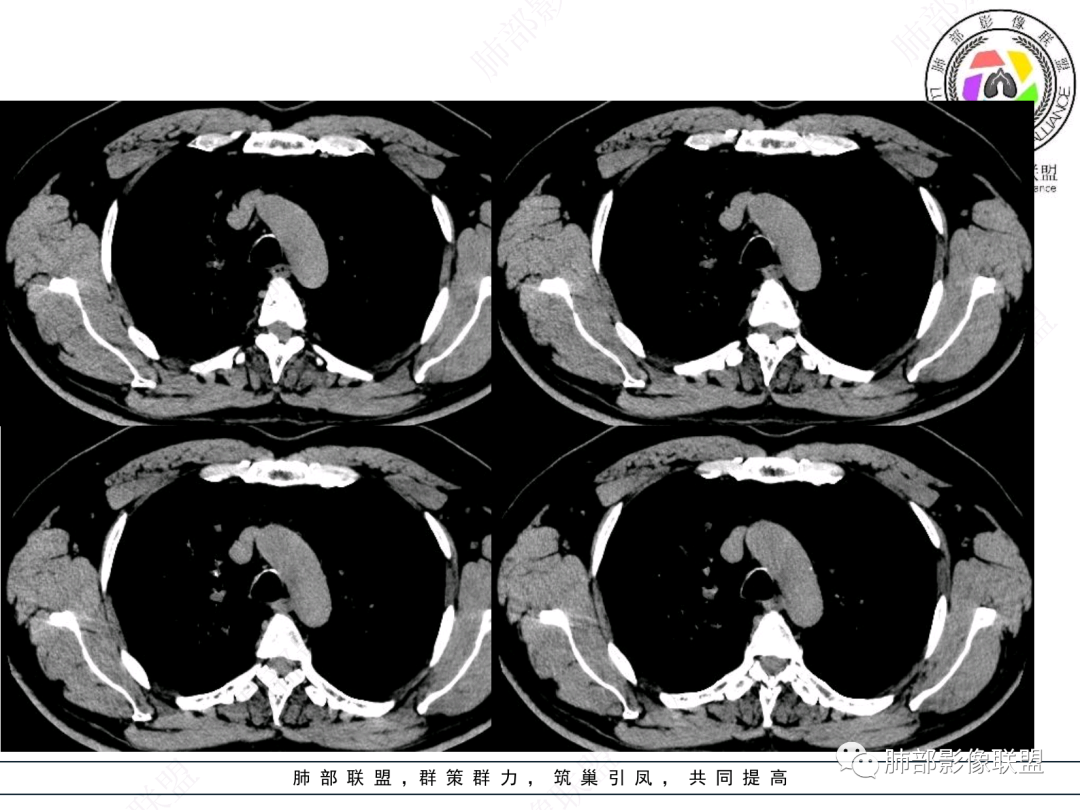

右肺上叶支气管截断,内见软组织密度结节,支气管管壁破坏,病变侵及管外,增强强化明显。右肺上叶沿气管血管束多发斑片影,考虑恶性性病变并阻塞性炎症,鳞癌,神经内分泌肿瘤。

右肺门病灶,支气管腔内堵塞,见有多处低密度影,支气管镜下凹凸不平,直观下不像鳞癌,恶性肯定的,考虑腺样囊性癌可能。

右肺主支气管-上叶支气管腔内结节伴钙化,轻度强化,考虑类癌,鉴别错构瘤与结核。

老年男性,咳嗽咳痰,右肺门增大,右主支气管开口见高密度影,密度不均匀,轻度强化,右肺上叶见多发腺泡结节,支气管管壁增厚,近端粘液栓,支气管镜检查见新生物,考虑鳞癌,鉴别结核。

右主支气管及肺门不规则软组织结节,点状钙化,不均匀强化,气管壁破坏,上叶支气管阻塞,分支粘液栓,血管束增粗,沿支气管分布多发结节,考虑鳞癌合并阻塞性炎症,鉴别结核。

右气管腔内结节,右肺门肿物,有钙化,右侧肺内多发气腔结节,散在,左肺部分支气管壁增厚,首先分析气管内结节,多考虑1鳞癌,形态规则,边缘光滑,宽基底,不太支持,远端阻塞性炎症不典型,2类癌,冰山一角和冰山分离了,不太支持3结核,多为支气管壁广泛增厚钙化,形成结节少,但是肺门肿块有钙化,可作为结核支持点,4黏痰,不像。其他不太懂了,肺内多发磨玻璃结节,并可见支气管手指状扩张,综合分析影像,考虑感染性病变,结核?有没有这样子的气管曲霉呢?向老师们学习。

老年男性,右肺门主支气管腔内软组织肿块影,密度不均,有钙化,右上叶支气管腔部分阻塞,强化较明显,右肺上叶远端散在斑片状高密度影,相应支气管壁厚,树丫状腺泡结节,常规首先考虑结核,鉴别类癌。

右主支气管占位,累及全层,中度强化,远端管壁增厚,似乎花花草草,恶或者低度恶性。疾病谱:鳞(必须首先考虑 概率),腺样囊腺癌(位置 年龄符合 似乎强化也符合),类癌(强化不太支持),良性,结核(妖)。综合考虑腺样囊腺癌。

男性,52岁,右侧主支气管腔内外占位伴点状钙化,病灶大部分位于腔外,右肺上叶散在结节影,气管腔内病灶,动脉期中度强化,静脉期强化减低,首先考虑气管腔内类癌可能,鉴别鳞癌,肺内病变倾向感染性病变;再有气管结核伴肺内播散。

男,52。间断咳嗽、咳痰2周,加重3天。胸部CT:右主、右上叶支气管多发软组织影,跳跃不连续,内可见小环状高密度,点状钙化,管壁破坏,上叶支气管堵塞,远端分支粘液栓,可见小支气管管壁增厚、管腔狭窄,沿支气管分布多发结节,无大片炎症不张。考虑:TB?NTM?鉴别Ca并阻塞性炎症。

这个病例比较好,我们的观察点在哪?这是右上叶支气管病变,需要了解:腔内、壁、腔外、远端,腔内有软组织密度影,近端膨隆。

红色:软骨连续性良好,壁外有软组织密度影,绿色:软骨不连续,破坏了,外面软组织密度影。

南边:提示软骨破坏,也就是病灶腔内朝壁外侵犯了——恶性。

远端支气管腔内不强化的是粘液栓,强化的是肿瘤。

影像上分析的观察点:腔内、壁、腔外、远端,然后就是远端肺组织、淋巴结、肺血管、胸膜、其他肺部,这个人就是阻塞性炎症为主。